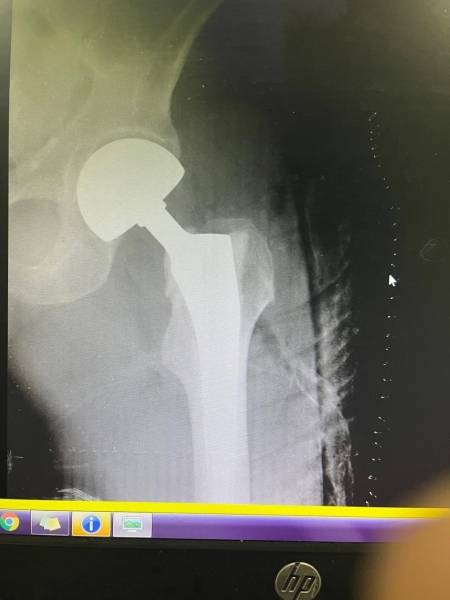

- إجراء عمليات جراحية معقدة و دقيقة في مجال العظام و المفاصل و الكسور و الإصابات ، رغم الضغط الكبير على المستشفى و أعداد المراجعين الكبيرة.

- تطبيق تقنيات جراحية حديثة و متقدمة، و ذلك في ظل التحديات التي يواجهها الفريق بسبب أعداد المرضى و المراجعين الكبيرة.